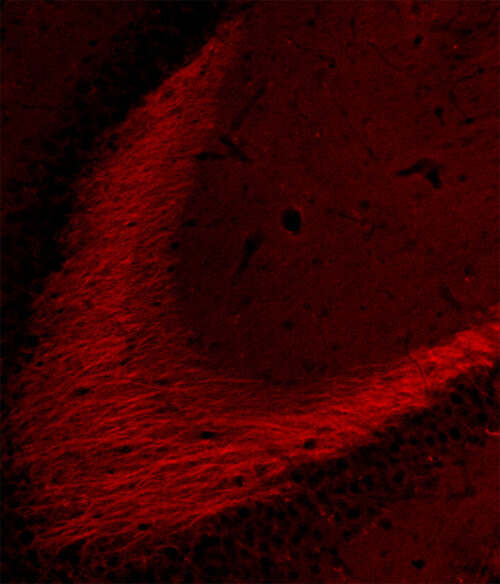

IHC: 1 : 500 gallery

Immunohistochemistry (IHC) on 4% PFA perfusion fixed tissue with 24h PFA post fixation. Immunoreactivity is usually revealed by fluorescence or a chromogenic substrate. Some antibodies require special fixation methods or antigen retrieval steps. For details, please refer to the ”Remarks” section.